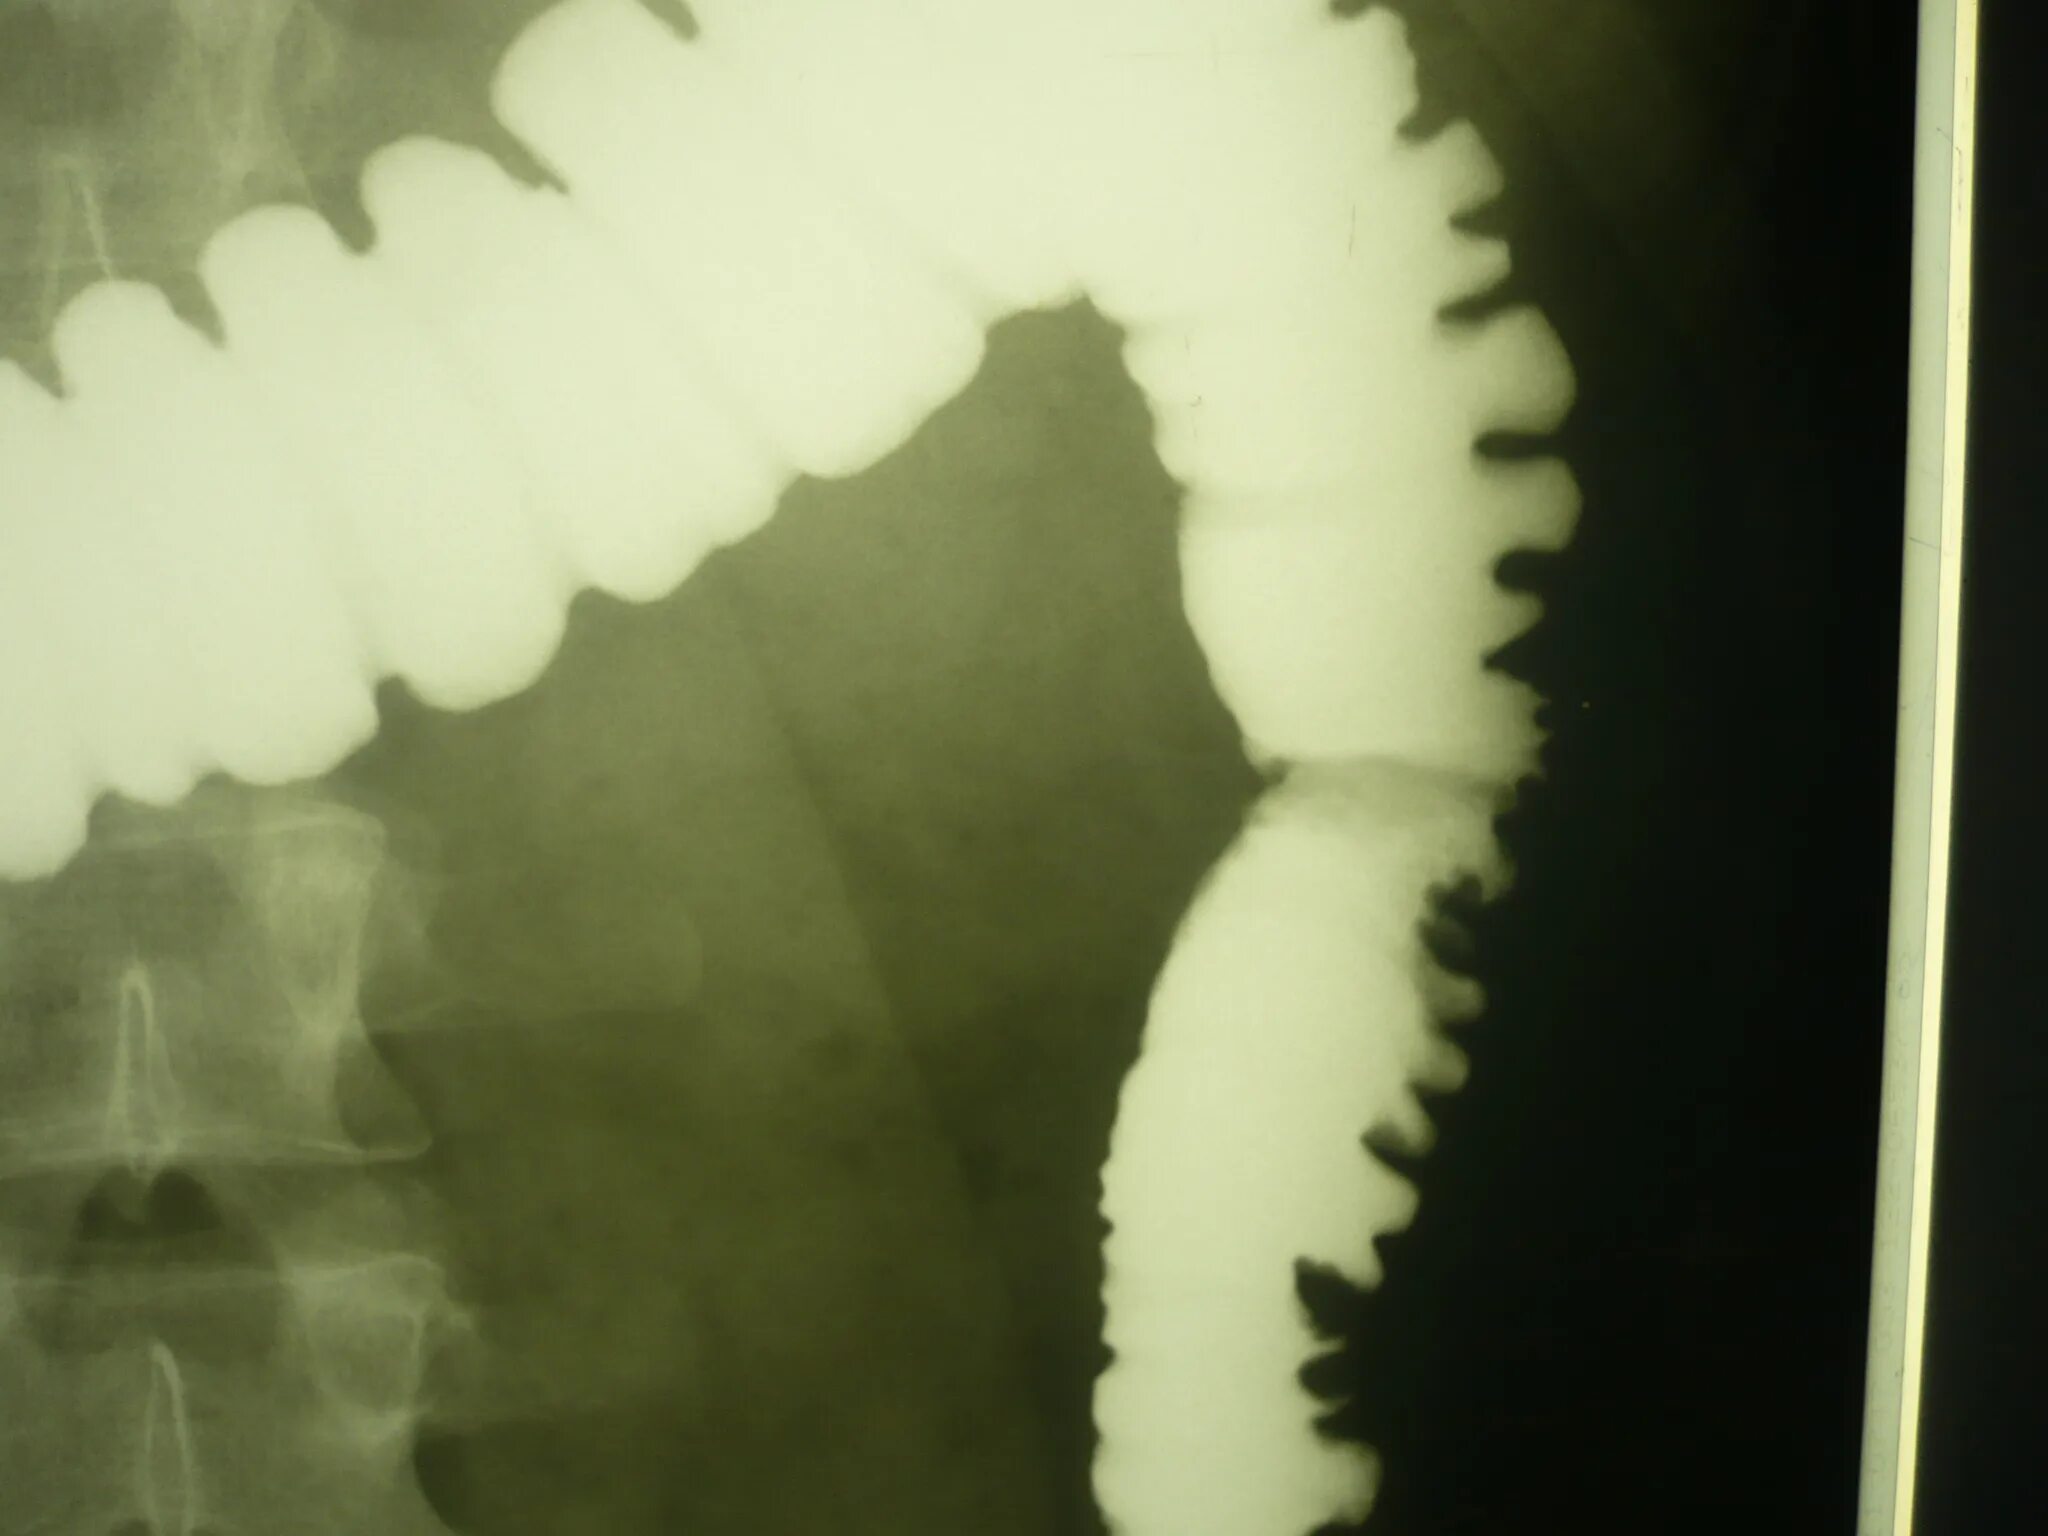

Кишечник после ирригоскопии